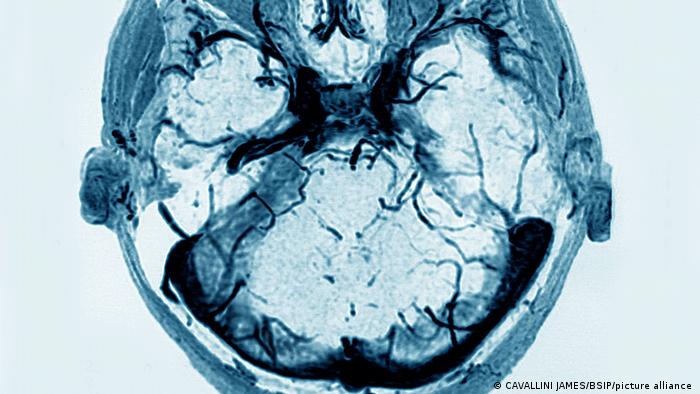

Η Επιτροπή Φαρμακοεπαγρύπνισης του ΕΟΦ συνεδρίασε εκτάκτως την Πέμπτη και οι επιστήμονες κατέληξαν σε προσωρινό πόρισμα για πιθανή συσχέτιση του εμβολίου της AstraZeneca με τα περιστατικά θρομβώσεων όσον αφορά στην περίπτωση ενός 35χρονου, αλλά και της 44χρονης γυναίκας που συνεχίζει να νοσηλεύεται στο ΠΑΓΝΗ.

Οι επιστήμονες κατέληξαν σε αυτό το προσωρινό πόρισμα καθώς ήδη έχουν ενημερωθεί προφορικά για το αποτέλεσμα του αντισώματος. Ο 35χρονος και η 44χρονη βγήκαν θετικοί σε ειδικό έλεγχο για παράγοντα που είναι χαρακτηριστικός του συνδρόμου θρόμβωσης και αιμορραγίας. Όταν τα αποτελέσματα φτάσουν και γραπτώς στην επιτροπή, θα καταλήξουν σε οριστικό πόρισμα.